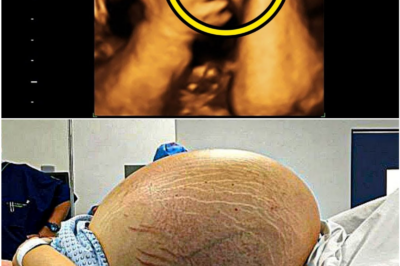

Expecting Twins, She Got the Shock of a Lifetime: The Ultrasound That Left a Doctor Speechless What began as a…